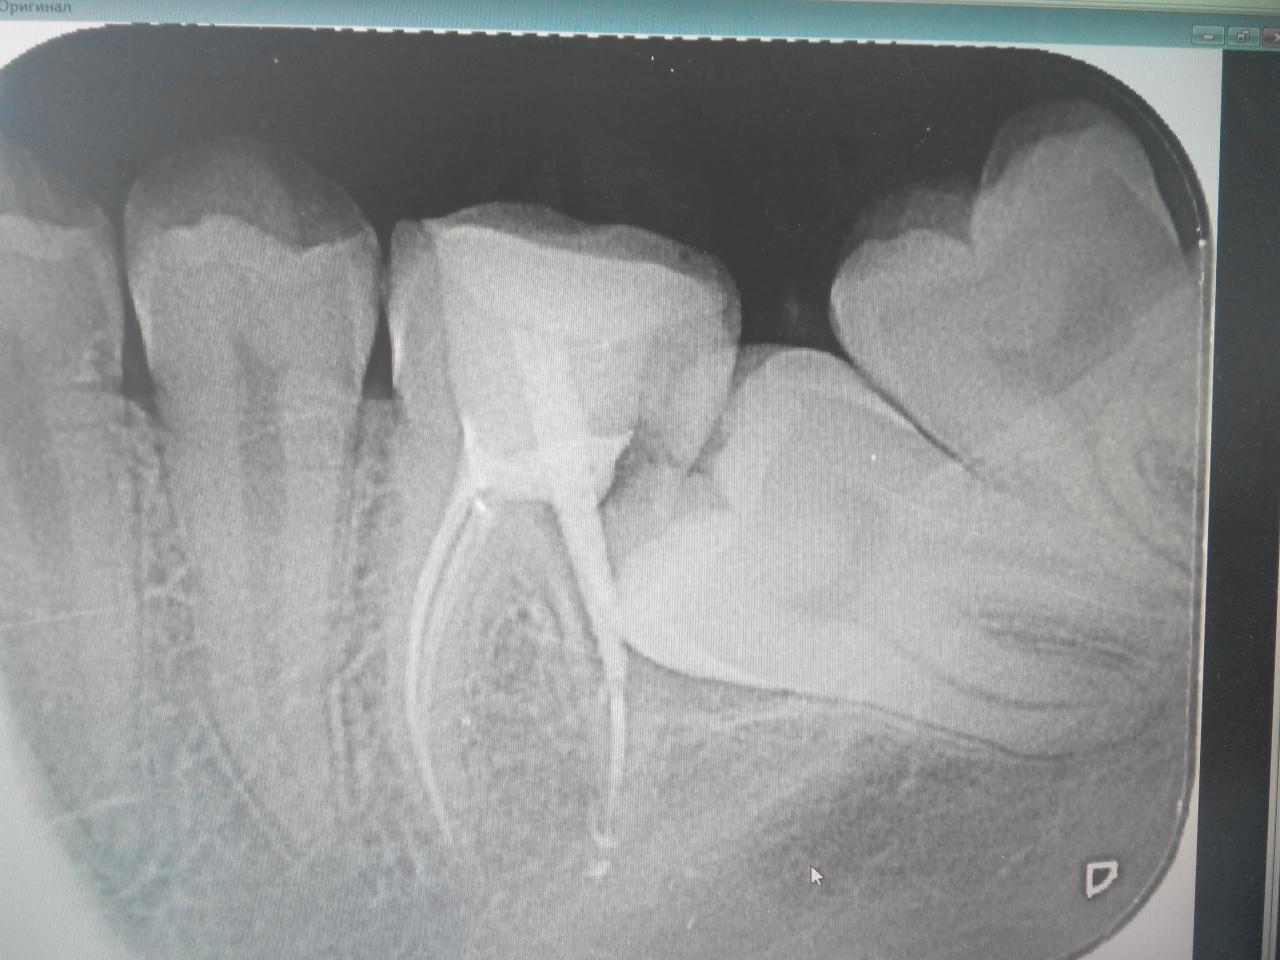

похоже?:

Нажмите на изображение для увеличения

Название: 2015403141102.jpg

Просмотров: 64

Размер:	121.7 Кб

ID:	9898237

и где вы такое берёте?

я, даже, сначала подумал, что это один и тот же пациент.

тактику сочиняли впятером.

в итоге, в данном конкретном случае принято такое решение:

- удаление 6 (уже сделано. было не просто)

- ортодонтическое перемещение 7 на место 6 и 8 на место 7.

а, самое главное чуть не забыл.

причина обращения! жалобы были: глубокий карман в области 6 зуба, запах, то сё... терапевты не справлялись.